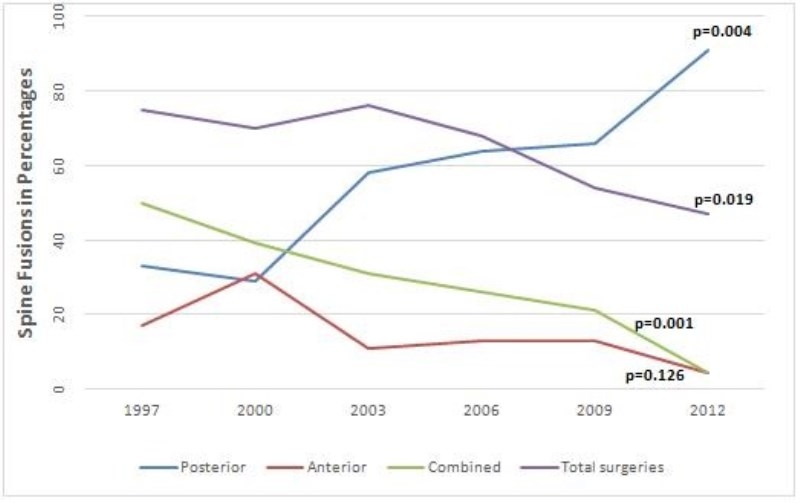

15年期间,共有897例EOIS患者,其中546例(61%)需要手术治疗。EOIS患者的脊柱畸形手术率显著下降(从1997年的75%到2012年的47%),P=0.019(图 1)。

图1 15年研究期内美国EOS手术术式趋势

手术方式上,62%(n=342)的患者行后路手术,13%(n=71)的患者行前路手术,24%(n=133)的患者行前后路联合手术。后路手术从1997年的33%显著增加到2012年的91%,(P<0.004)。前后路联合手术从50%降至4.3%(P<0.001)。前路手术也从17%降到4.3%,(P<0.126),但此无统计学意义。